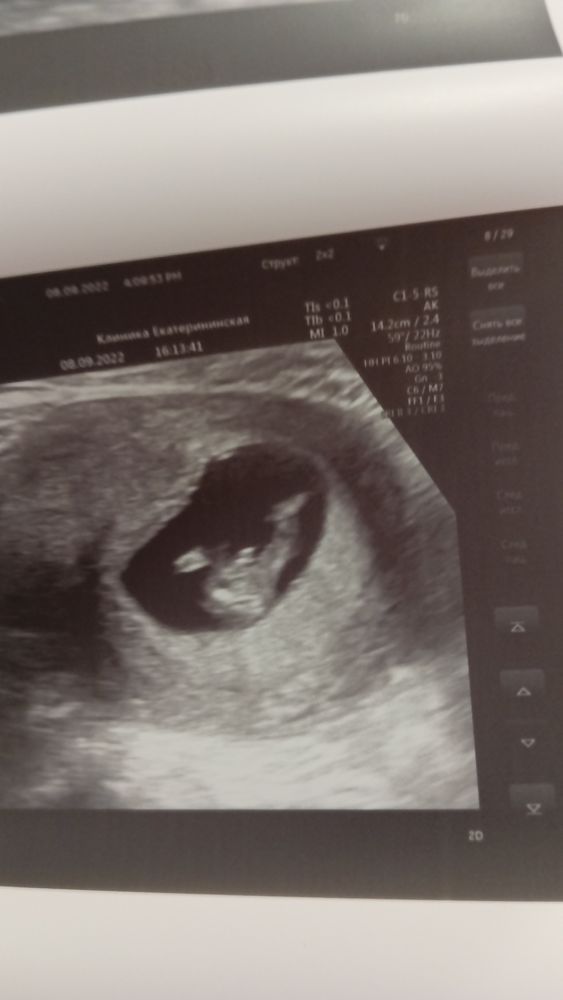

Изображение Тут 16недель по М по узи 15 второй сынок